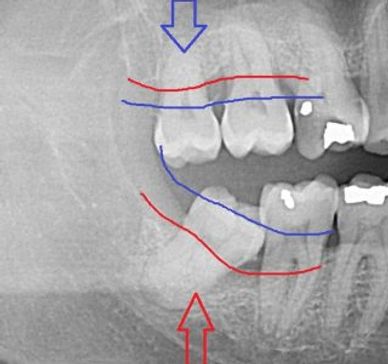

As wisdom teeth come in between the ages of 17 and 25, its best to monitor their growth and potential impact for not being able to come into place. Determination of when to remove wisdom teeth is NOT based on age, it is based on development of your jaws with respect to the wisdom teeth AND the developmental progress of the roots.

We recommend removal of wisdom teeth that have 1/2-3/4 root development that won't have enough space to come in. Wisdom teeth removal at this point is very quick with extremely low risk of complications. Because the surgery and anesthesia are separate jobs (versus one provider doing two jobs), the appointment for this is safer, always painless, and always memory-free on every patient, every time.